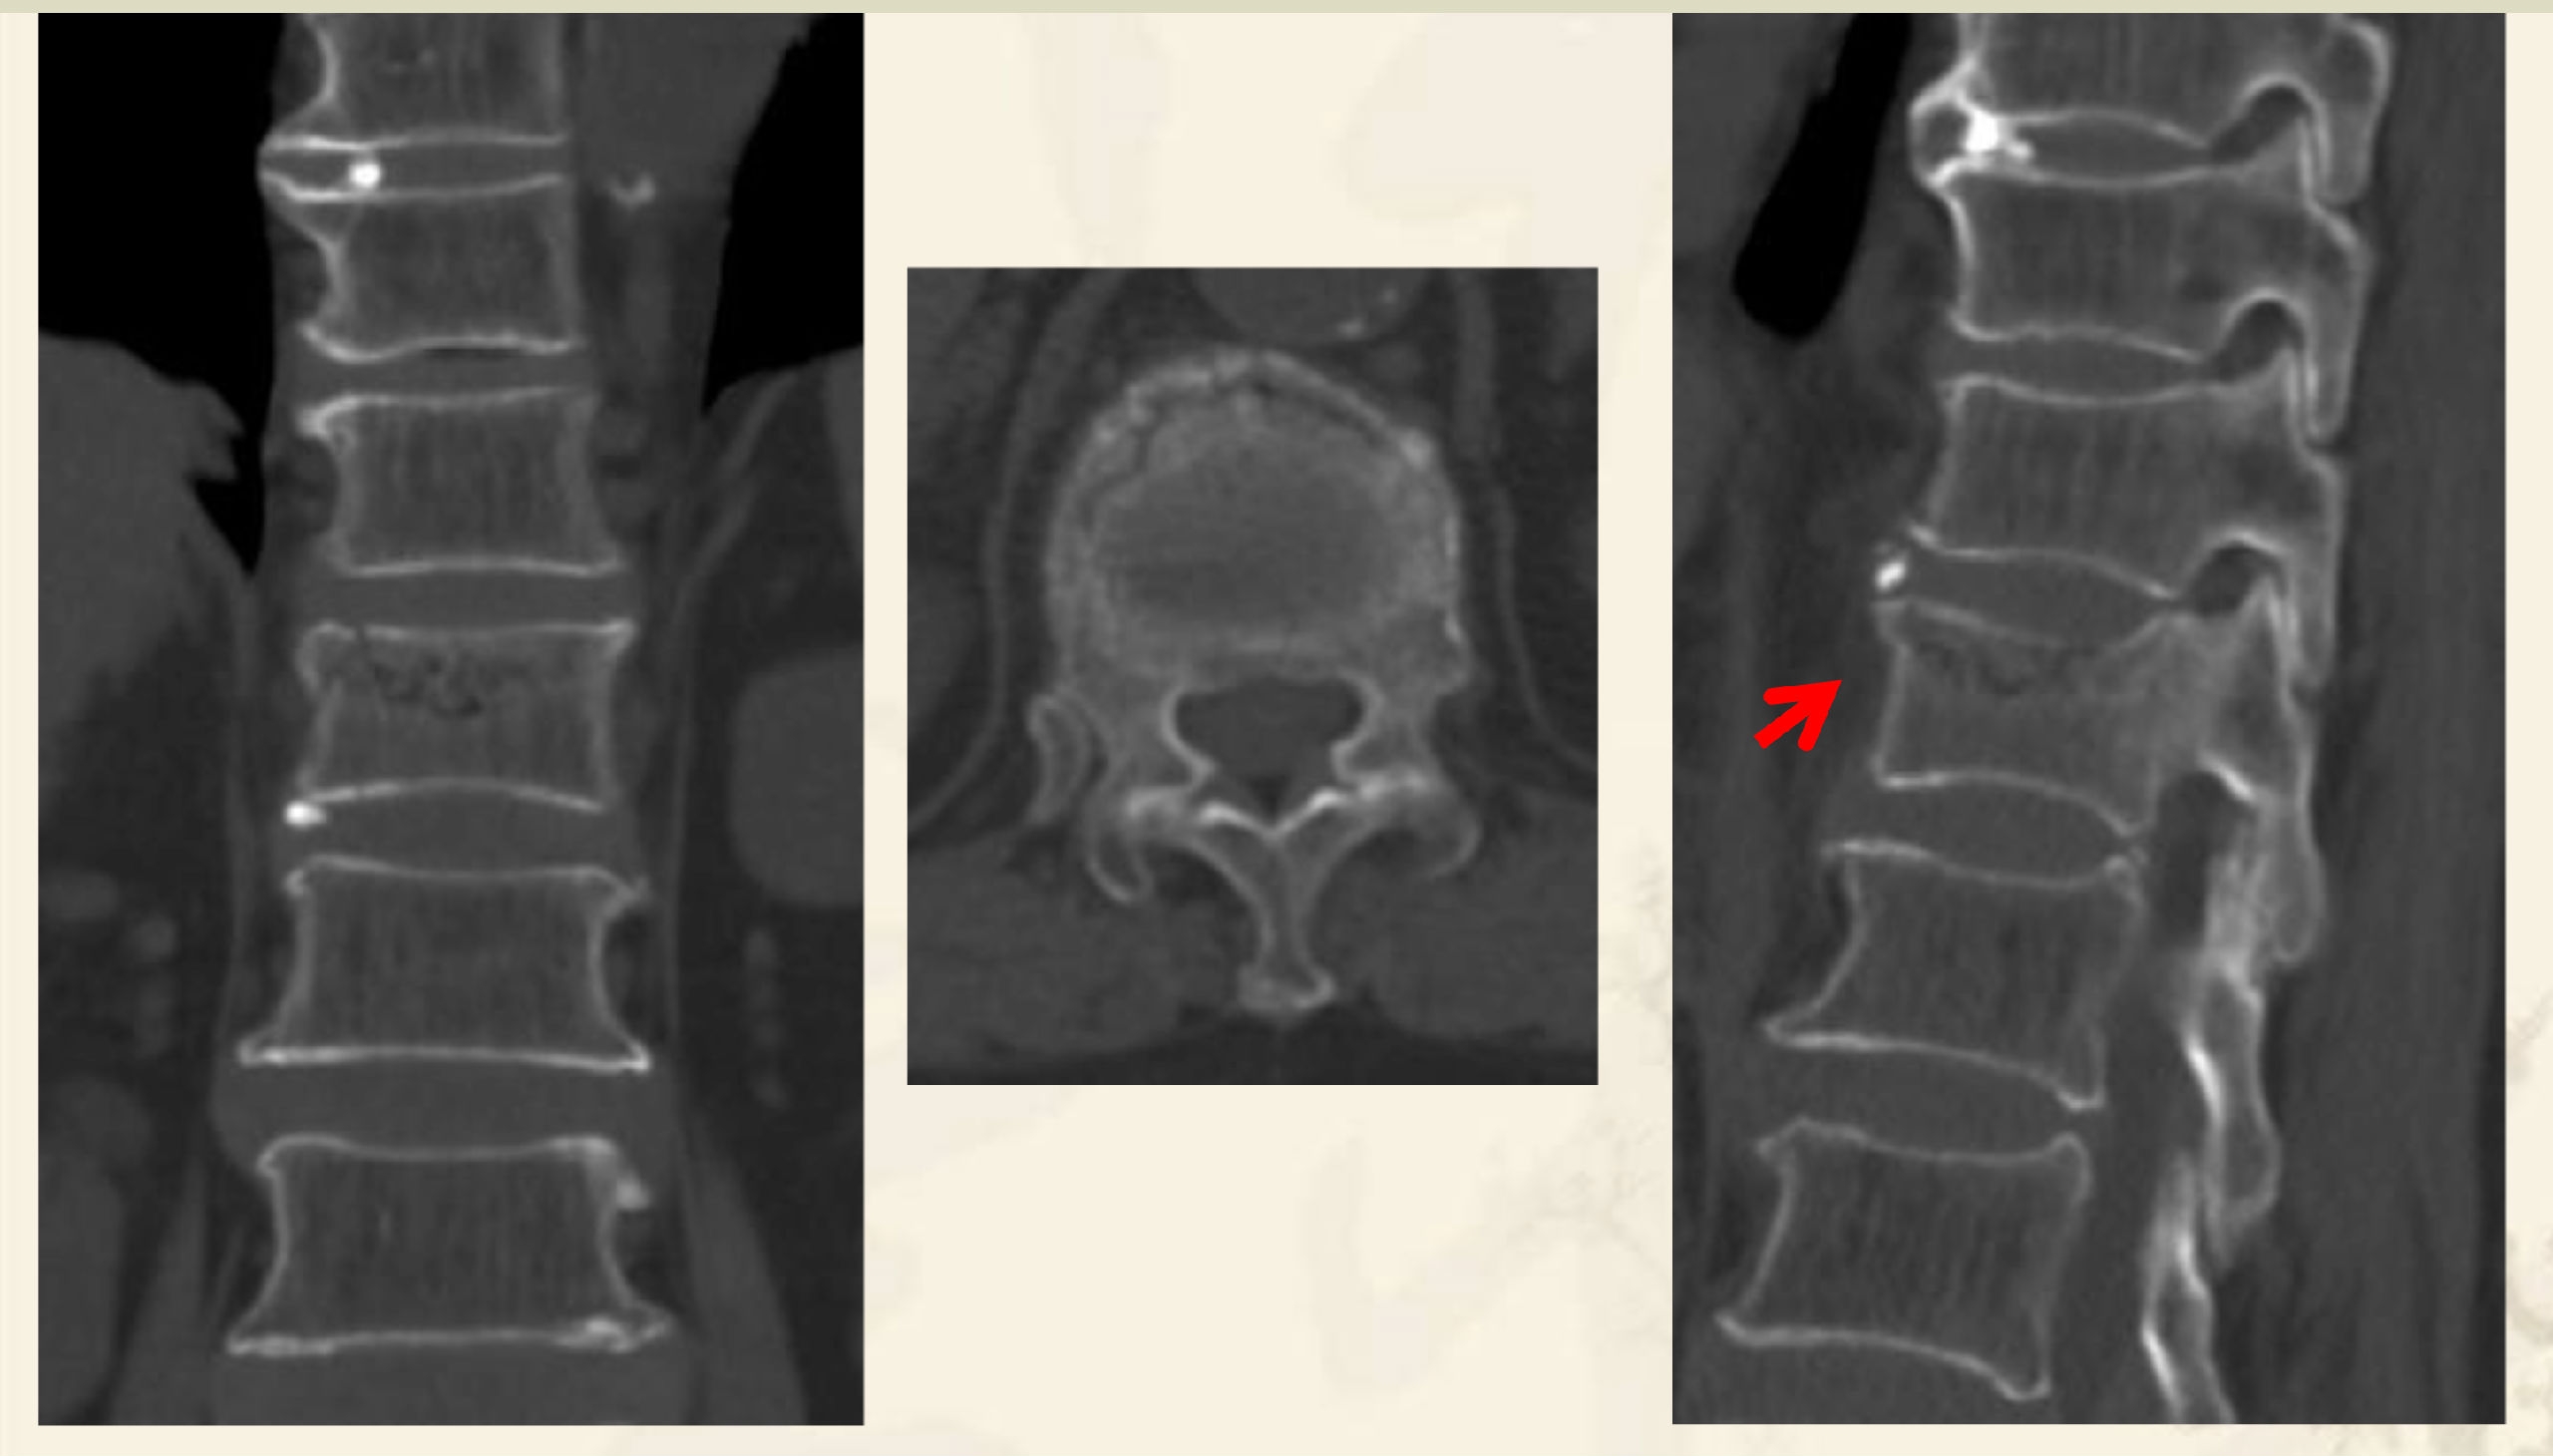

压缩后嵌插型骨折线,CT:高密度带、MRI低信号带。

压缩后自动复位裂隙型,CT:裂隙,MRI:低信号区(气体)

压缩后自动复位裂隙型

CT:裂隙,MRI:高信号区(液体)

术前CT